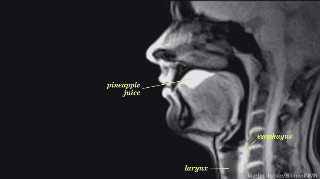

1. Bebiendo jugo de piña.